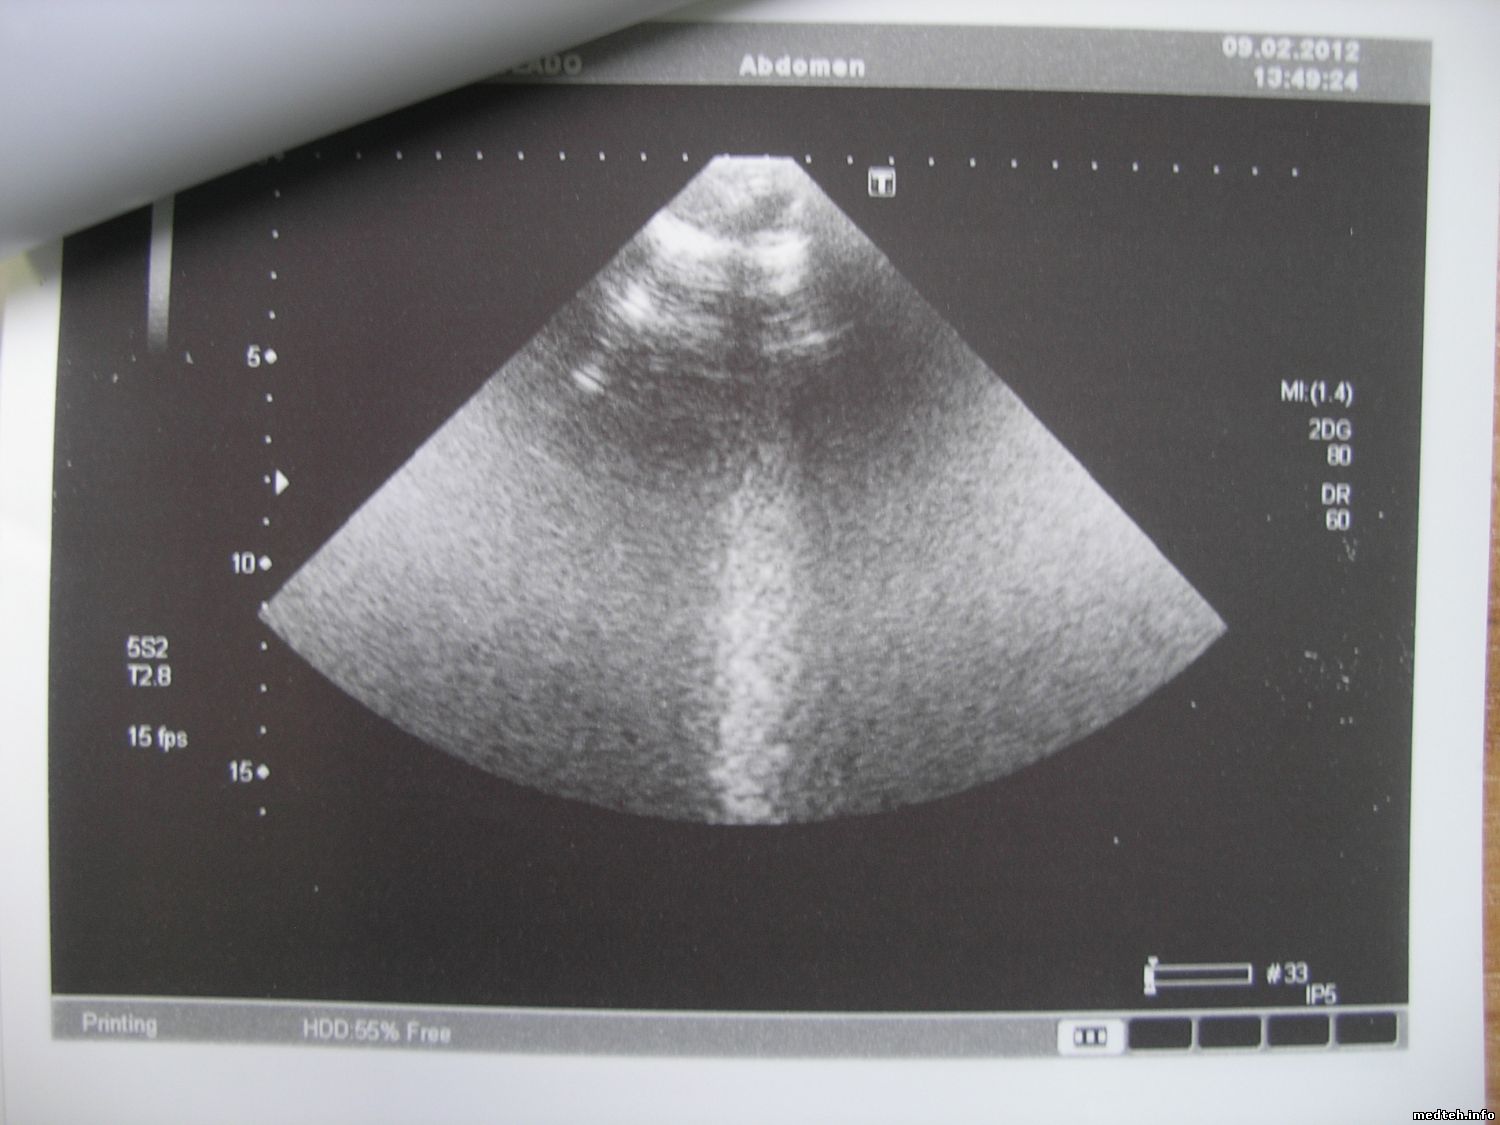

| Форум медтехников Медицинское оборудование (тех. разделы) УЗИ оборудование Помехи на УЗ-изображении... (БЕЗ ПРИВЯЗКИ К КАКОМУ_ЛИБО ПРОИЗВОДИТЕЛЮ) |

| Помехи на УЗ-изображении... | |||||||||